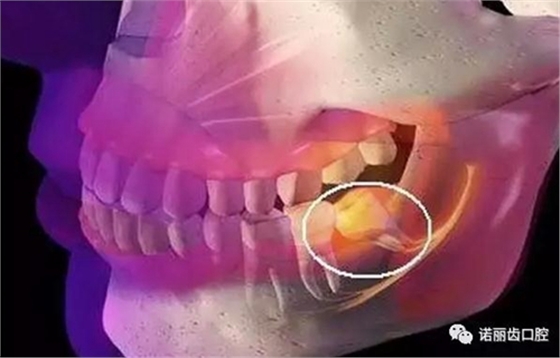

阻生智齒

這是比較常見的一種問題,該種智齒通常埋在齒槽骨的里面,如果經(jīng)常發(fā)生炎癥,或是診斷會有病灶發(fā)生的時候,就必須拔除。